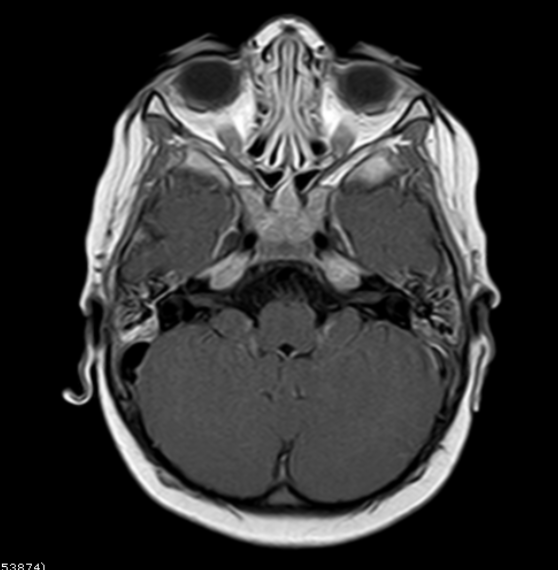

¿Cuál de los siguientes enunciados considera más correcto respecto a los hallazgos de la resonancia magnética (RM)?: